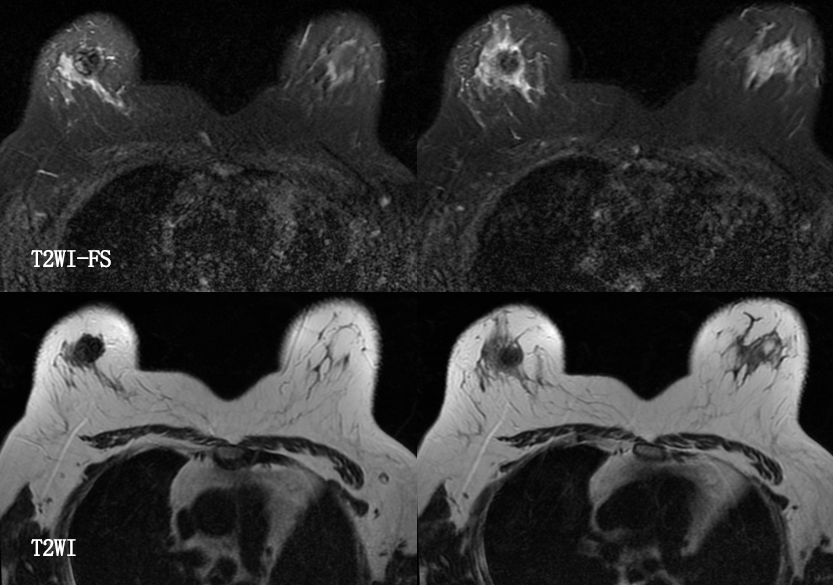

MG/CT: